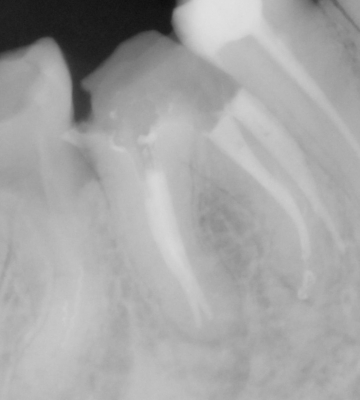

PRZYKŁADY LECZENIA KANAŁOWEGO WYKONANEGO PRZEZ NASZ ZESPÓŁ

Przykłady odstępstw anatomicznych kanałów zębowych